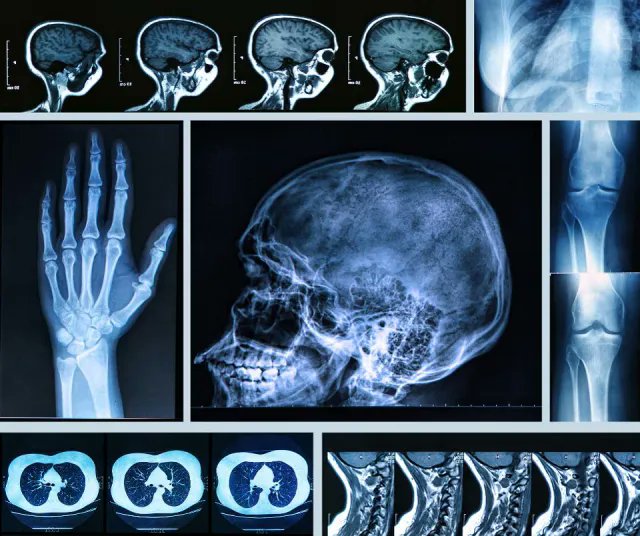

Перепутали рентген

Перепутали рентген 117 фотографий